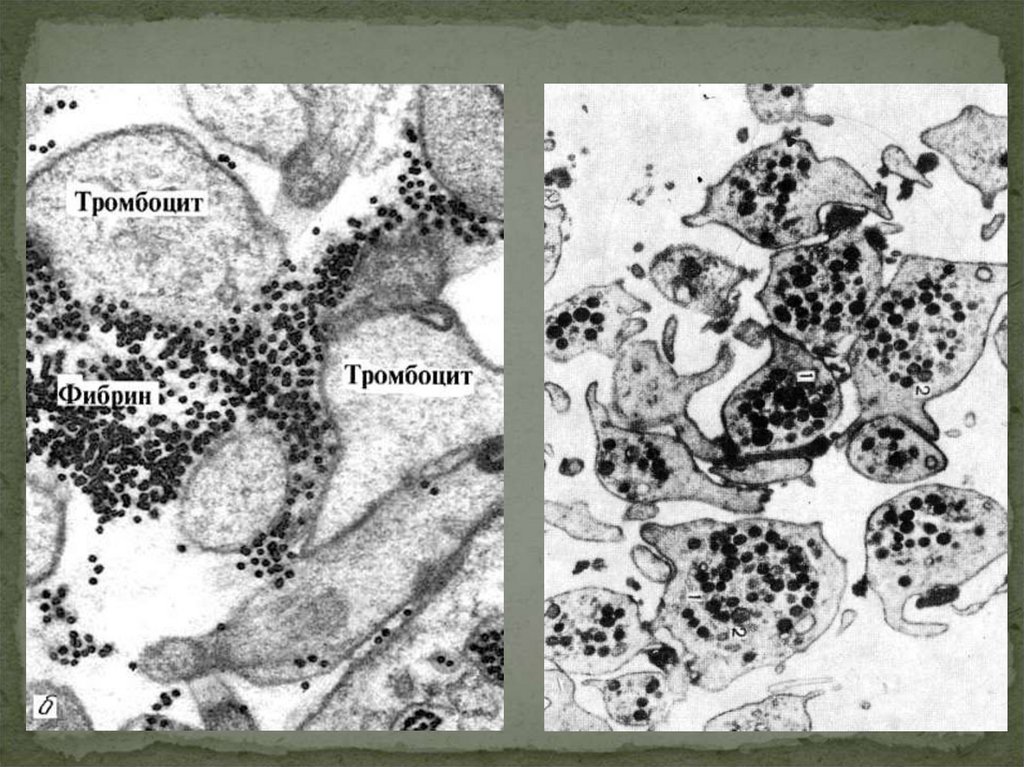

37. ОБРАЗОВАНИЕ ТРОМБОЦИТОВ

38.

39.

40.